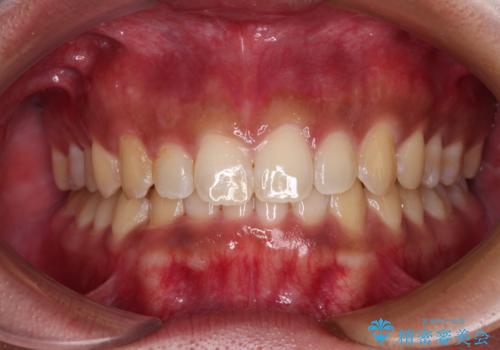

上下前歯の前歯と腫れやすい歯肉 インビザライン矯正で改善

ディープバイトとデコボコを解消 インビザライン矯正

デコボコとディープバイトを治したい インビザラインによる矯正治療